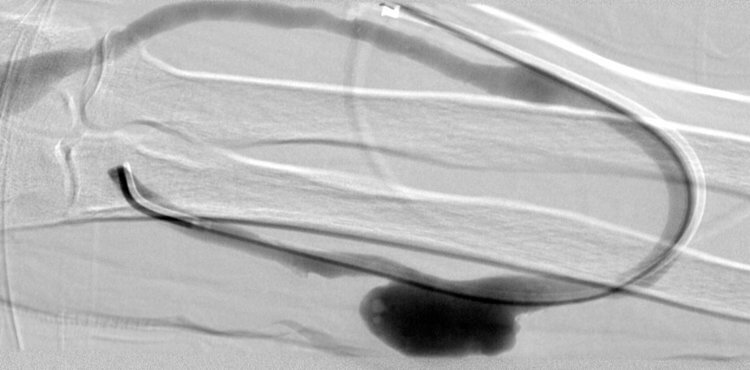

50 year old male with chronic kidney disease on hemodialysis who presents with a pseudoaneurysm of the arterial limb of a RUE arteriovenous dialysis graft.

Comment: Repeated punctures into an arteriovenous graft can potentially lead to pseudoaneurysm formation. In some cases, bleeding through the skin can result. When this occurs, options for treatment include revising the graft or placement of a covered stent in the affected limb of the graft. This is what was done in this case. Two stents were placed across the pseudoaneurysm to insure that they were adequately anchored in the graft both proximal and distal to the pseudoaneurysm. Once they were deployed and post-dilated, the pseudoaneurysm was effectively excluded.